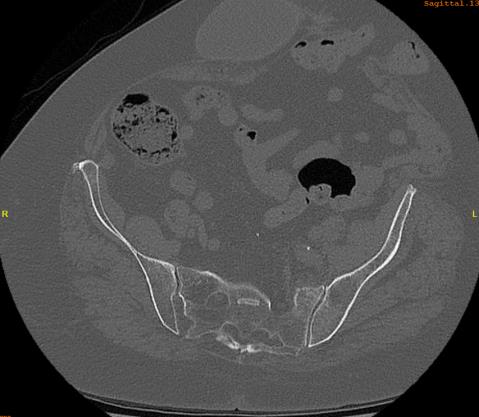

Rommens and Hofmann Classification (CT)

Type I: Anterior pelvic ring only (17.5%)

Type II: Non displaced posterior pelvic ring (50%)

Type III: Displaced unilateral posterior pelvic ring (10%)

Type IV: Displaced bilateral posterior pelvic ring (20%)